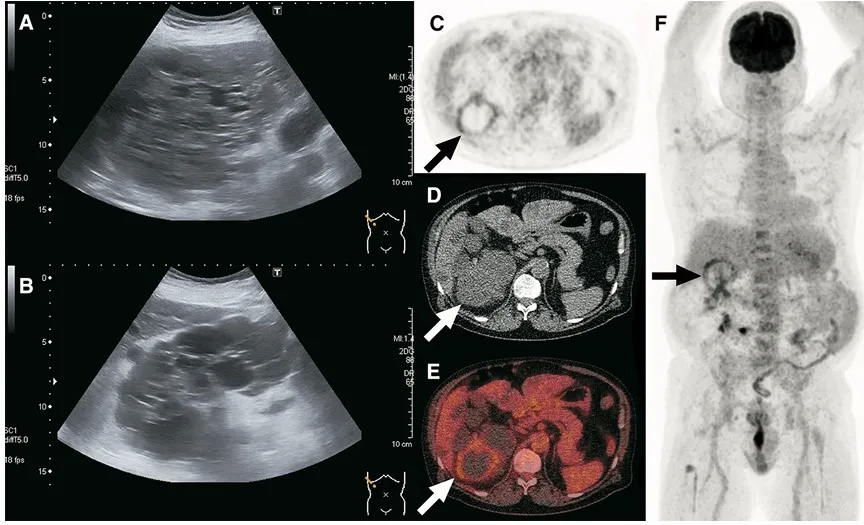

O 18F-FDG PET/CT surge como ferramenta de maior especificidade, útil para localizar o(s) cisto(s) infectado(s) e definir o alvo da punção.

📚 Na série de casos da imagem abaixo (**[link](https://link.springer.com/article/10.1007/s40336-017-0261-8)**), é possível ver como o PET/CT-FDG orienta a conduta e modifica o manejo em infecções renais e hepáticas na DRPAD.